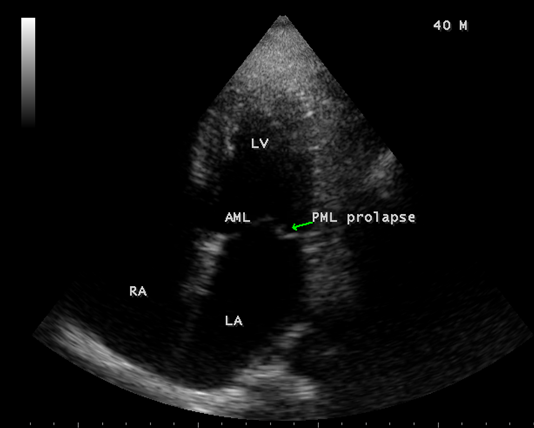

Case 1. PML (posterior mitral leaflet) prolapse causing mitral regurgitation without LA (left atrium) enlargement as shown in Figures 1 and 2 (non-rheumatic) in a 40-year old male. The patient was advised lifelong penicillin prophylaxis and periodic follow up.

Figure 1. Apical four chamber view showing the PML (posterior mitral leaflet) prolapse (non-rheumatic) in a 40-year-old male. Left atrium (LA) not dilated.